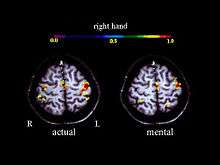

Neurophysiological mechanisms

A large number of functional neuroimaging studies have demonstrated that motor imagery is associated with the specific activation of the neural circuits involved in the early stage of motor control (i.e., motor programming). This circuits includes the supplementary motor area, the primary motor cortex, the inferior parietal cortex, the basal ganglia, and the cerebellum.[15][16] Such physiological data gives strong support about common neural mechanisms of imagery and motor preparation.[17]